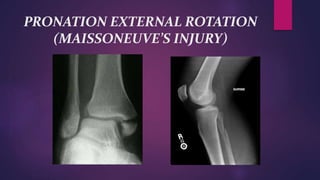

PRONATION EXTERNAL ROTATION

(MAISSONEUVE’S INJURY)

 If the deforming force continues to rotate the

fibula it will relax the posterior tibiofibular

ligament

 Either resulting in the spiral fracture of the

fibula just above the level of the syndesmosis

or may be as high as the neck of fibula-

Partial diastasis of the inferior tibio fibular

joint which is known as Maisonneuve’s

injury.